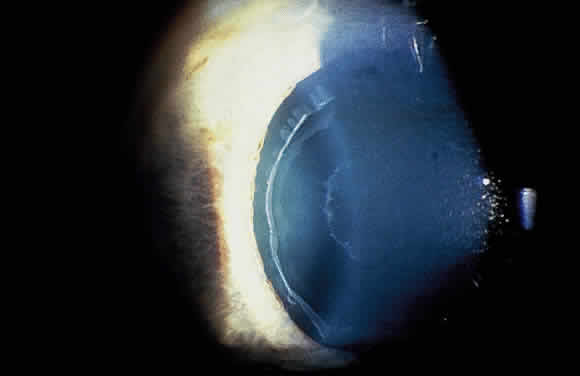

Deposition of exfoliative material on the anterior lens surface is the most commonly recognized feature of XFS and usually is best appreciated after pupillary dilation.43 A bull's-eye pattern generally is seen in which a translucent central zone and a granular peripheral zone of deposition are separated by an intermediate clear zone (Fig. 1). The translucent central zone of exfoliative material varies in diameter and may exhibit curled edges. In approximately 20% of patients with exfoliation, the central zone may be absent.38 The intermediate clear zone presumably results from lens contact with movement of the iris. The granular peripheral zone, which may be subtle but invariably is present in XFS, generally exhibits a well-delineated inner border and often shows numerous radial striations (Fig. 2). Occasionally, a bridge of exfoliative material may cross the clear zone to join the central zone and the granular peripheral zone.38,44

Fig. 1. Typical bull's-eye pattern of exfoliation on lens surface showing separation of central and peripheral zones of deposition by intermediate clear zone.